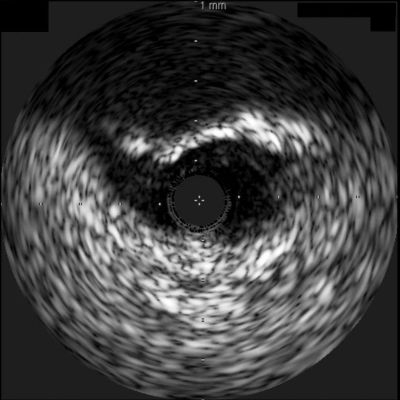

Right femoral arterial access was obtained, and SMA was engaged using a 6-French IMA guide catheter. Angiogram showed a 99% heavily calcified proximal SMA stenosis with a patent celiac artery (Image 2A). A BMW wire was used to cross the proximal SMA lesion. Multiple balloons were tried, but were unable to cross the lesion. Turnpike and Finecross catheters were attempted for Rotawire exchange without success. The lesion was then crossed with a Rotawire. A 1.5 mm RotaPro burr was used to perform two passes of rotational atherectomy for 110 seconds. The Rotawire was exchanged for a Grandslam wire using a Finecross catheter. Balloon angioplasty was performed with 4.0 x 27 mm and 5.0 x 20 mm noncompliant Trek balloons. IVUS showed severe nodular calcific stenosis with fractures in calcium (Image 3). After vessel sizing, a 6.0 x 29 mm Omnilink stent was deployed in ostial-proximal SMA. Post-dilation was performed with a 6.0 x 20 mm Dorado balloon. Final angiography showed the reduction of stenosis to 20% with significantly improved flow (Image 2B). The patient had an uneventful recovery and complete symptom resolution.